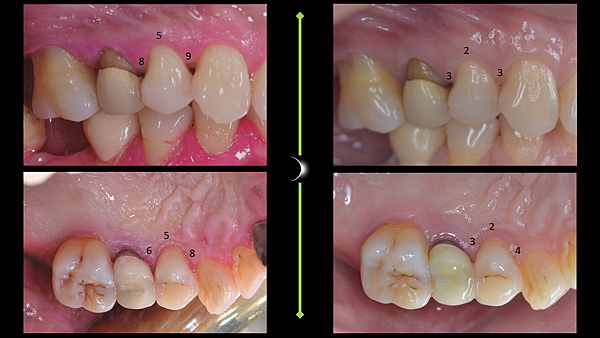

完美的牙周治療就是符合今日吾輩追求健康的兩大目標:功能與美觀

牙周囊袋深度降低到4mm以下

骨質密度增加

美觀的部分則為最少的牙齦萎縮,甚至像這個病例整體癒合非常良好,帶動了牙齦向上爬升

而如此完美的結果,莊醫師是以不開刀也不補骨的方式達成,在顯微鏡下以雷射與其他精細的工具進行牙齦下根面清創